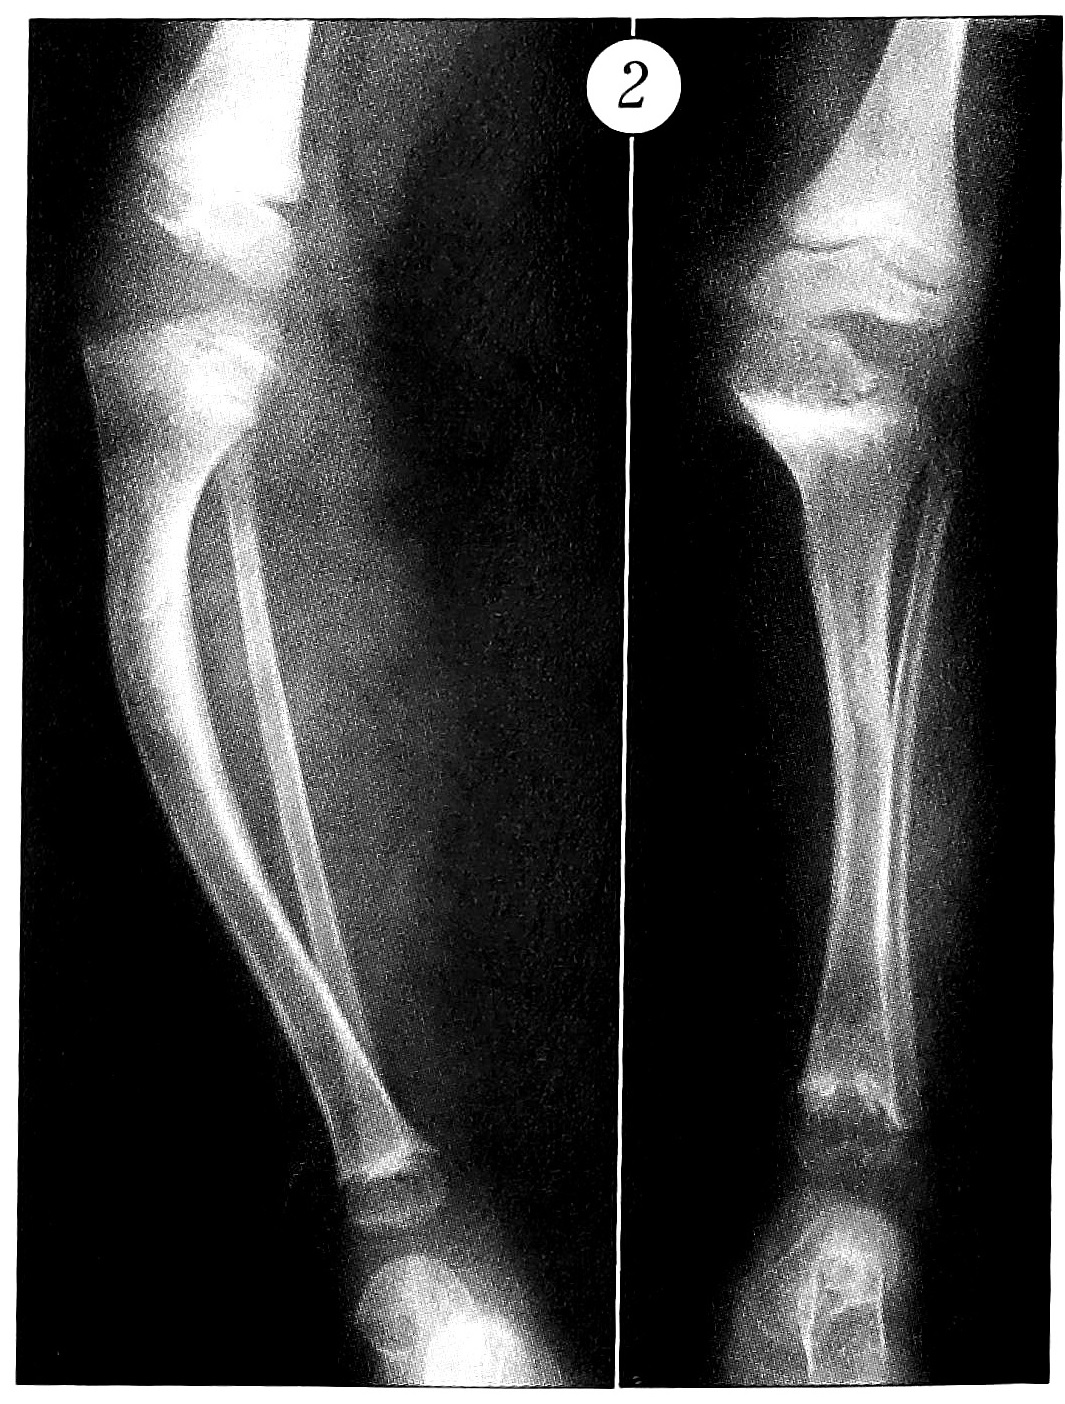

Рис. 1. Рентгенограммы коленного сустава больной Ч. Диагноз: диастрофическая дисплазия. а — в возрасте 3 лет; б — в возрасте 9 лет (сформировался наружноротационный подвывих в коленном суставе на фоне не устраненного вывиха надколенника); в — в возрасте 10 лет (после вправления вывиха надколенника и коленного сустава).

Почти у 40% наблюдавшихся детей консервативное лечение не проводилось или было абсолютно недостаточным. Оно ограничивалось назначением массажа, рекомендациями родителям самим заниматься с ребенком лечебной гимнастикой и не предусматривало использования этапных гипсовых повязок, курсов физиотерапии, применения хондропротекторов и препаратов, улучшающих микроциркуляцию и течение обменных процессов. У 22% больных лечение этапными гипсовыми повязками проводилось, наоборот, чрезмерно долго — на протяжении 6-10 мес. Между тем, по нашим наблюдениям, при тяжелых деформациях максимальный эффект от такого лечения достигается в первые 2-3 мес. Далее прогрессируют остеопороз, атрофия мягких тканей, а контрактуры существенно не уменьшаются. При длительном лечении разгибательных контрактур коленного сустава этапными гипсовыми повязками мы отмечали у 85% больных вторичные деформации эпифизов и ретрокурвацию большеберцовой кости. До начала подобного лечения, а также в случаях, когда оно вообще не проводилось, частота таких деформаций составляла лишь 16%. У детей с гипермобильным синдромом резко возрастал риск развития вторичных деформаций, в частности стопы-качалки при лечении косолапости. Поэтому мы считаем, что через 2-3 мес такого лечения необходимо переходить к использованию съемных гипсовых лонгет, и особенно туторов, обеспечивающих более надежную фиксацию, а также ставить вопрос об оперативном вмешательстве. Попытки отложить его могут привести к тяжелым последствиям — подвывихи в коленном суставе переходят в вывихи со смещением костей голени проксимально на 8-10 см, в результате не устраненного подвывиха надколенника может сформироваться наружноротационный подвывих костей голени (рис.1).